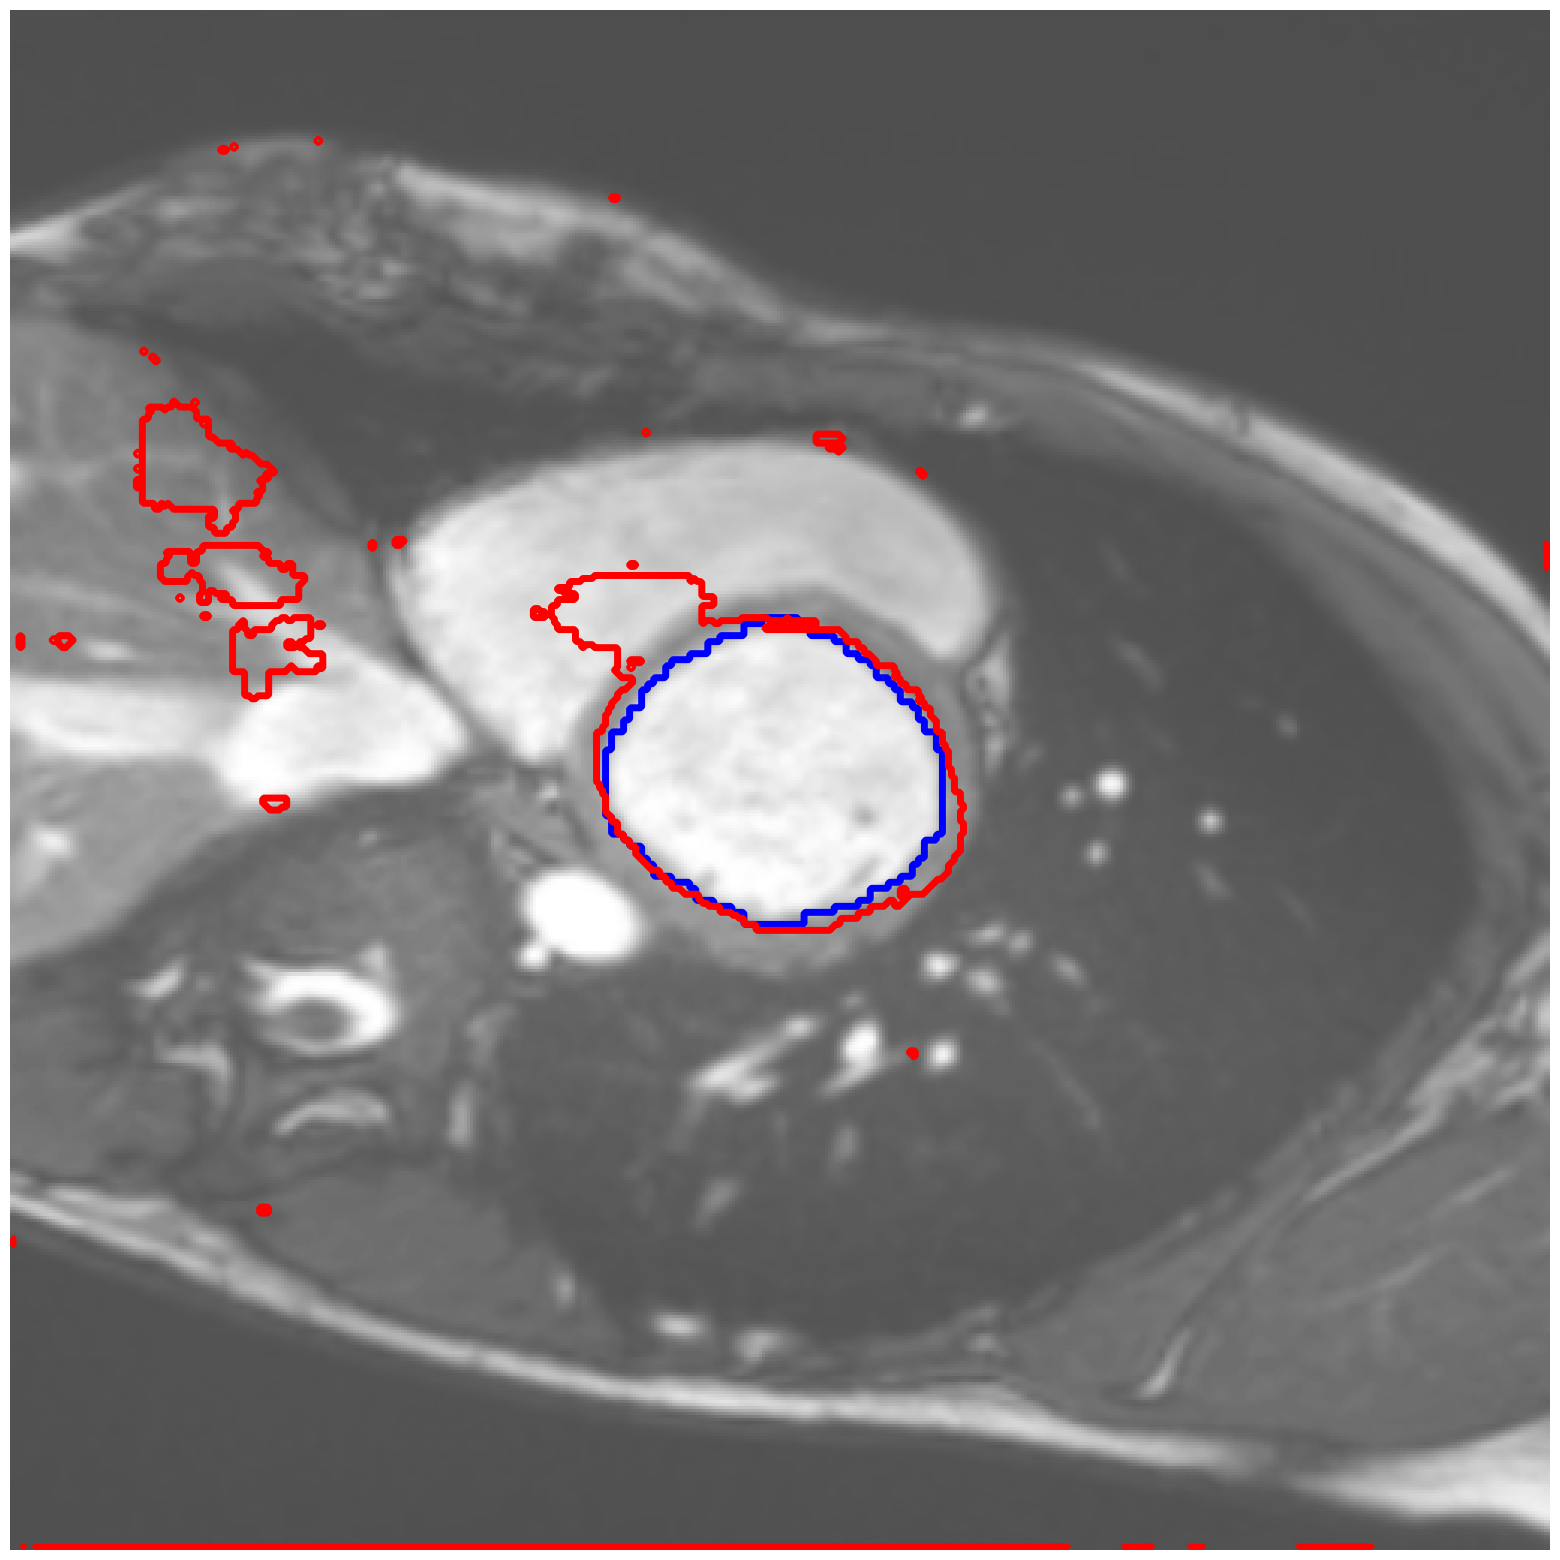

|

ACDC-RV |

![]() |

| (a) Original pred. | b) Consema | ——— c) Standard CRC ——— | ——— d) RW-CP (Ours) ——— | |||

Visually, we observe in Fig. 1 that RW-CP is able to produce prediction sets much closer to the ground-truth than standard CRC or Consema. Our approach is even able to remove small over-segmentated areas, whereas methods such as Consema can only increase the size of the prediction set, even when the segmentation model produced false positives.

We hypothesize that the performance of RW-CP stems from its pre-processing step on probabilities, which mitigates the overconfidence commonly observed in deep learning segmentation models [16]. Their raw softmax probabilities are often skewed towards either 0 or 1 (see Fig. 1.c). This overconfidence compresses the effective range of possible values for the empirical threshold used in Conformal Risk Control, making the final prediction mask extremely sensitive to small fluctuations in . On the contrary, by first applying a diffusion process, the pixel-wise probabilities become more varied and less polarized (as shown in Fig. 1.d). This broadened distribution stabilizes the empirical during calibration, leading to a more robust and tighter prediction set, which translates to better overall segmentation metrics